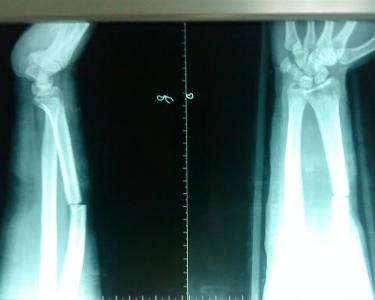

盖氏骨折(Galeazzi fracture)为桡骨中下1/3骨折合并下尺桡关节脱位,曾有许多称谓。早在1929年法人称之为反孟氏骨折,其后还被称为Piedmont骨折,Compbell则称之为fracture of necessity(必须骨折),因其确信此种损伤必须手术治疗。 1934年Galeazzi详细描述了此种损伤,并建议牵引拇指整复之。此后即习惯称此种损伤为盖氏骨折。盖氏骨折是一种常见损伤,其发生率较孟氏骨折多6倍。